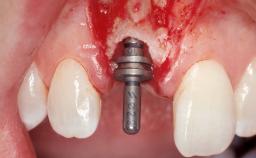

Immediate Flapless Placement of an Implant in a Maxillary Left Central Incisor Site

A 42-year-old female patient was referred to our clinic at the School of Dentistry of the University of São Paulo in November 2004, presenting a deficient restoration in the upper left central incisor. The clinical examination revealed no gingival retraction or any signs of gingival inflammation and, therefore, previous periodontal treatment was not considered. The patient presented a high lip line at full smile and a thin tissue biotype. This combination characterized a high-risk situation from an anatomic point of view, which required careful preoperative planning and cautious surgical execution.

Placement Protocol Immediate implant placement

Loading Protocol Immediate

Retention Screw-retained Screw-retained